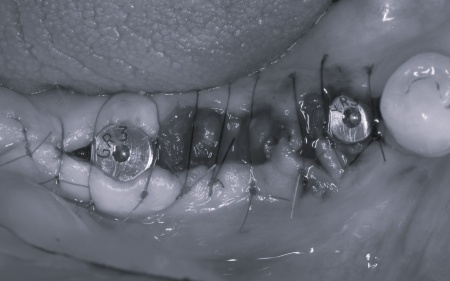

まず、右下奥歯(第2小臼歯、第1大臼歯)を抜きます。

周囲の骨や歯茎への影響をできるだけ抑えるよう配慮しながら処置を行い、抜歯した部位にインプラントを埋め込みました。

抜歯後にできた穴とインプラントの間には隙間が生じるため、骨の再生を助ける目的で骨補填材を使用しながら、丁寧に縫合しました。